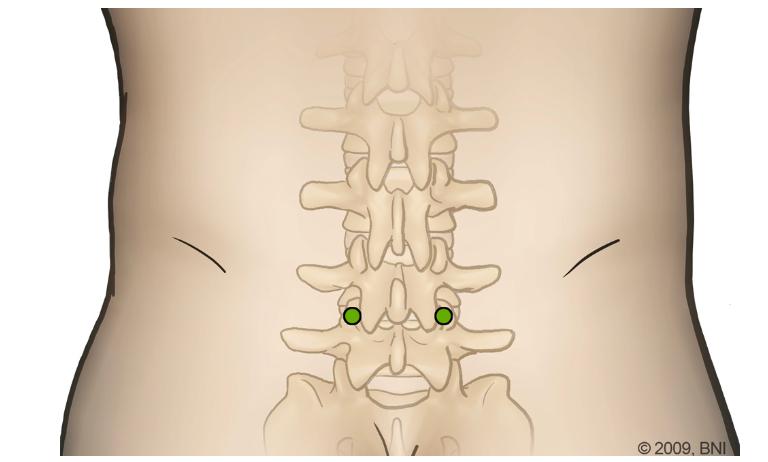

Figure 6: Illustration of Minimally Invasive PLIF A) Entry points, B) dilatorsusedinmusclesplittingtechnique

9

A B

MINIMALY INVASIVE POSTERIOR LUMBAR INTERBODY FUSION

Steps

Typically utilises endoscopic and microscopic tubular dilators,retractors,bed-mountedflexiblearm

1

2

Positioning:(a)Prone,(b) onaJacksontable

Operative Level Identification: following identification, a 2-4cm midline incision is made and a Steinmann pin is passed until the medial borderofthefacetjointisreached

3

Extension of incision: the skin incision is then extended 2-3cm above and below the Steinmann pin.

4

Visualisation: serial dilators are used to split muscle layers Once muscle layers are split and visualisation is sufficiently achieved, the final channelisfixedtotheflexiblearmretractor,which is mounted to the table side rail subsequently, dilatorsareremoved

5

Exposure, laminotomy, removal of ligamentum flavumperformed.

6 Interbodygraftispositionedintodiscspace

Distraction:small interbody distractor devices are insertedintothediscspaceandrotatedtodistract the disc space and restore intervertebral height Distractionofthecontralateralsideissubsequently performedinasimilarfashion

7

8

Bone graft is then packed anteriorly in the disc space and additionally packed around and within theremainingfacet